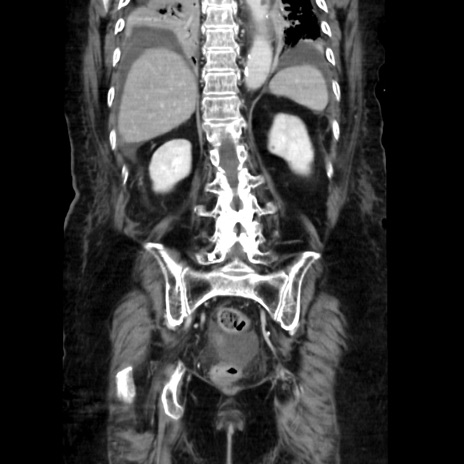

症例40(冠状断像)

【症例】90歳代女性

【主訴】腹痛・嘔吐

【現病歴】 食欲低下、嘔吐があり昨日他院受診。肺炎と診断され入院となる。入院後より腹部全体に圧痛あり。胃管留置され経過みていたが、症状持続するため、

当院転院となる。

【既往歴】胸椎圧迫骨折、胆石症

【身体所見】腹部:中央に激痛あり、圧痛あり、反跳痛不明

【データ】WBC 17100、CRP 18.82

冠状断像